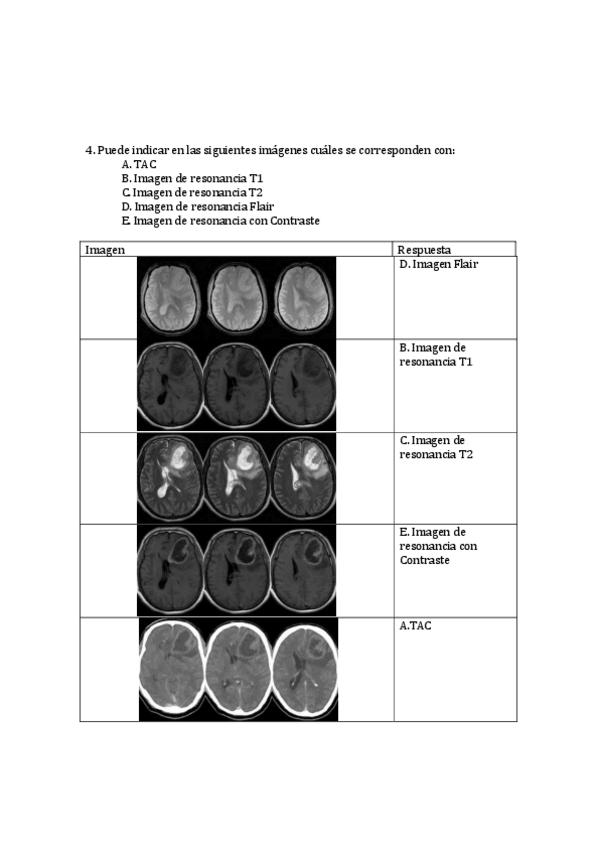

He publicado nuevos apuntes de 4º Neuropsicología Clínica: Tarea-Neuroimagen.pdf

3 páginas

He publicado nuevos apuntes de 4º Neuropsicología Clínica: Tarea-Neuroimagen-.pdf

He publicado nuevos trabajos de 4º Neuropsicología Clínica: Tarea-Neuroimagen.pdf

Tarea-Neuroimagen.pdf